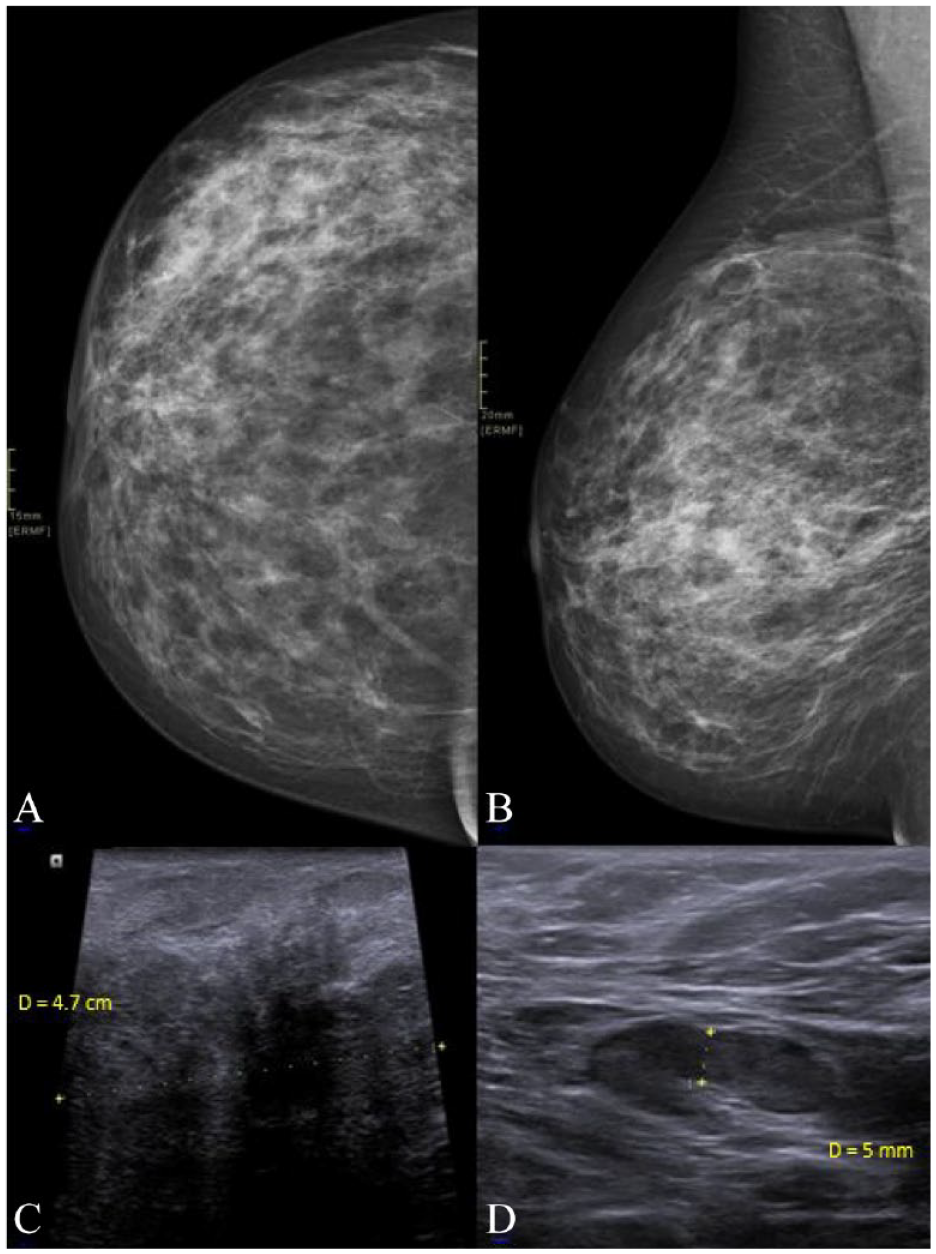

Mammography and breast ultrasound revealed a 7-cm nodular and irregular area involving the right breast at 8 o’clock (Figure 1A and B). In addition, there was a suspicious right axillary lymph node 21 mm (Figure 1 C and D). However, no abnormalities were detected in the left breast. Biopsy of the breast mass showed widespread acute inflammation, abscess formation, and fat necrosis (Figure 2).

Craniocaudal (A) and mediolateral oblique views (B) of the right breast show an area of increased density along the outer slightly lower quadrant of the right breast. Ultrasound (C) of this region showed an area of decreased echogenicity with areas of low-level internal echoes. Aspiration of the areas with low-level internal echoes revealed pus, which was sent for cytology and culture. Ultrasound of the right axillary region (D) showed a borderline 2 × 1 cm lymph node with 5 mm cortical thickening.